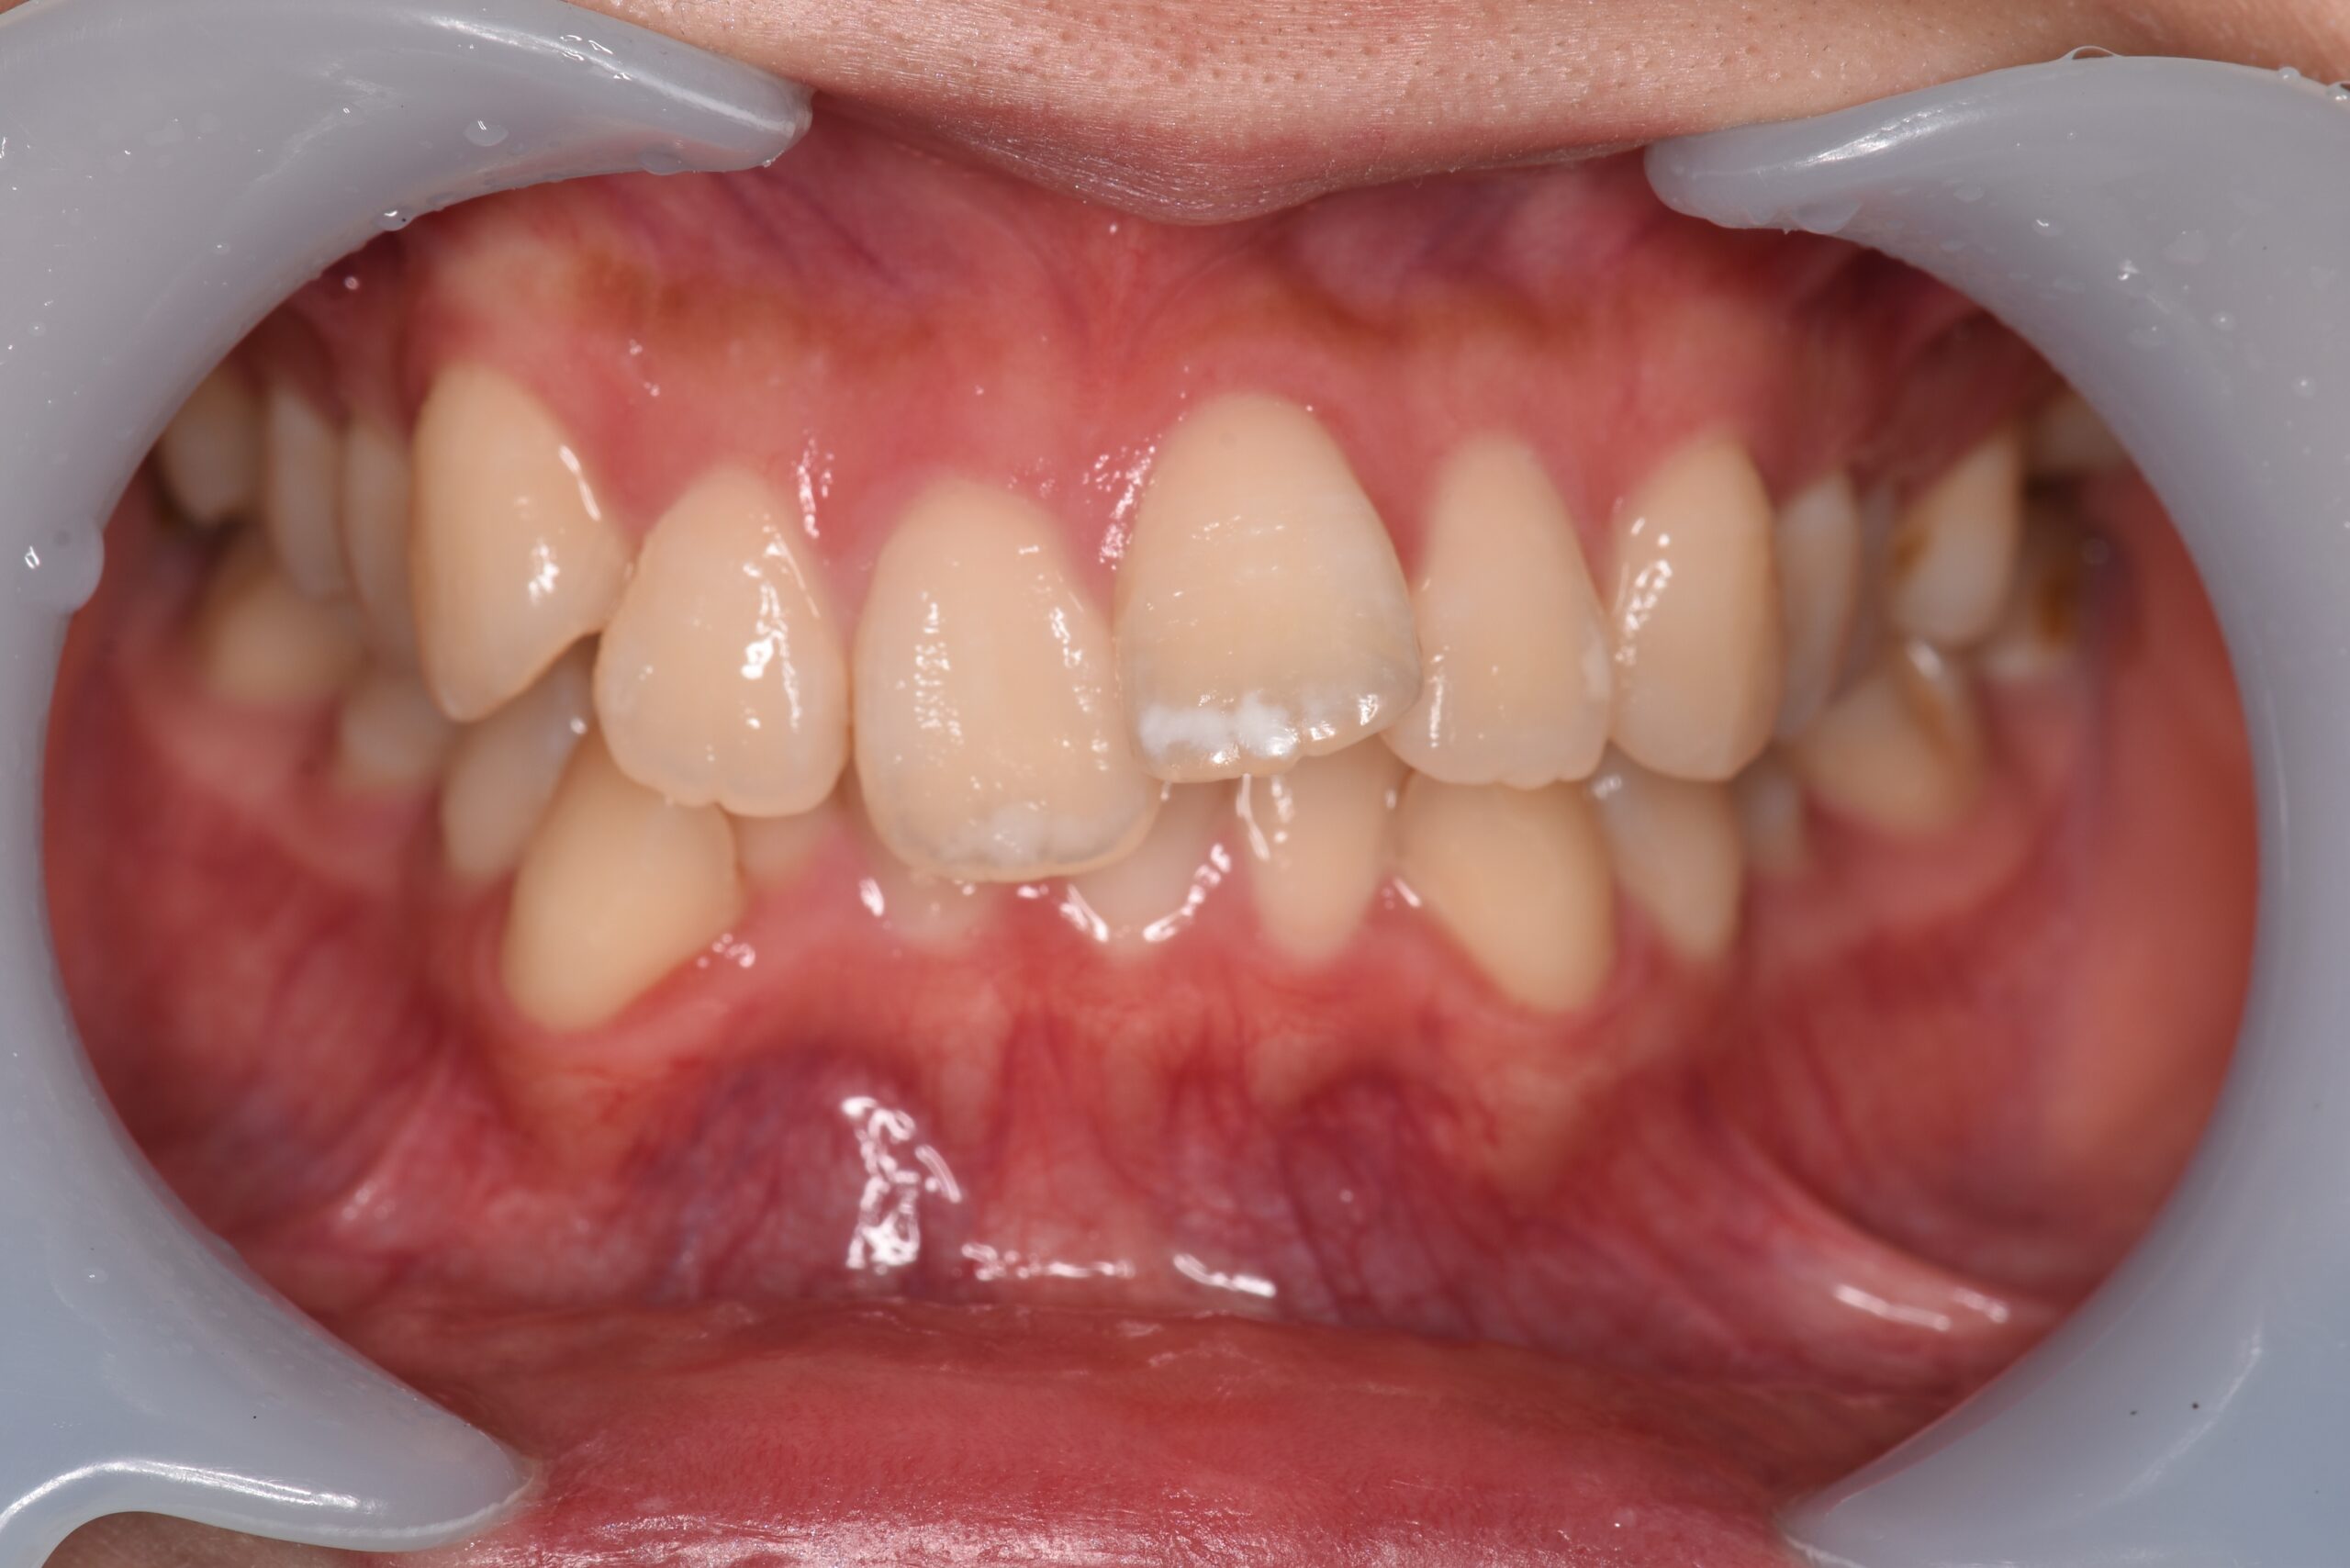

歯と歯の間に隙間がある状態です。

食事のときにうまく噛みきれなかったり、食べ物が歯に詰まりやすくなるなどのデメリットの他に、歯と歯の間から空気が抜けることで、発音にも支障が出るケースもあります。